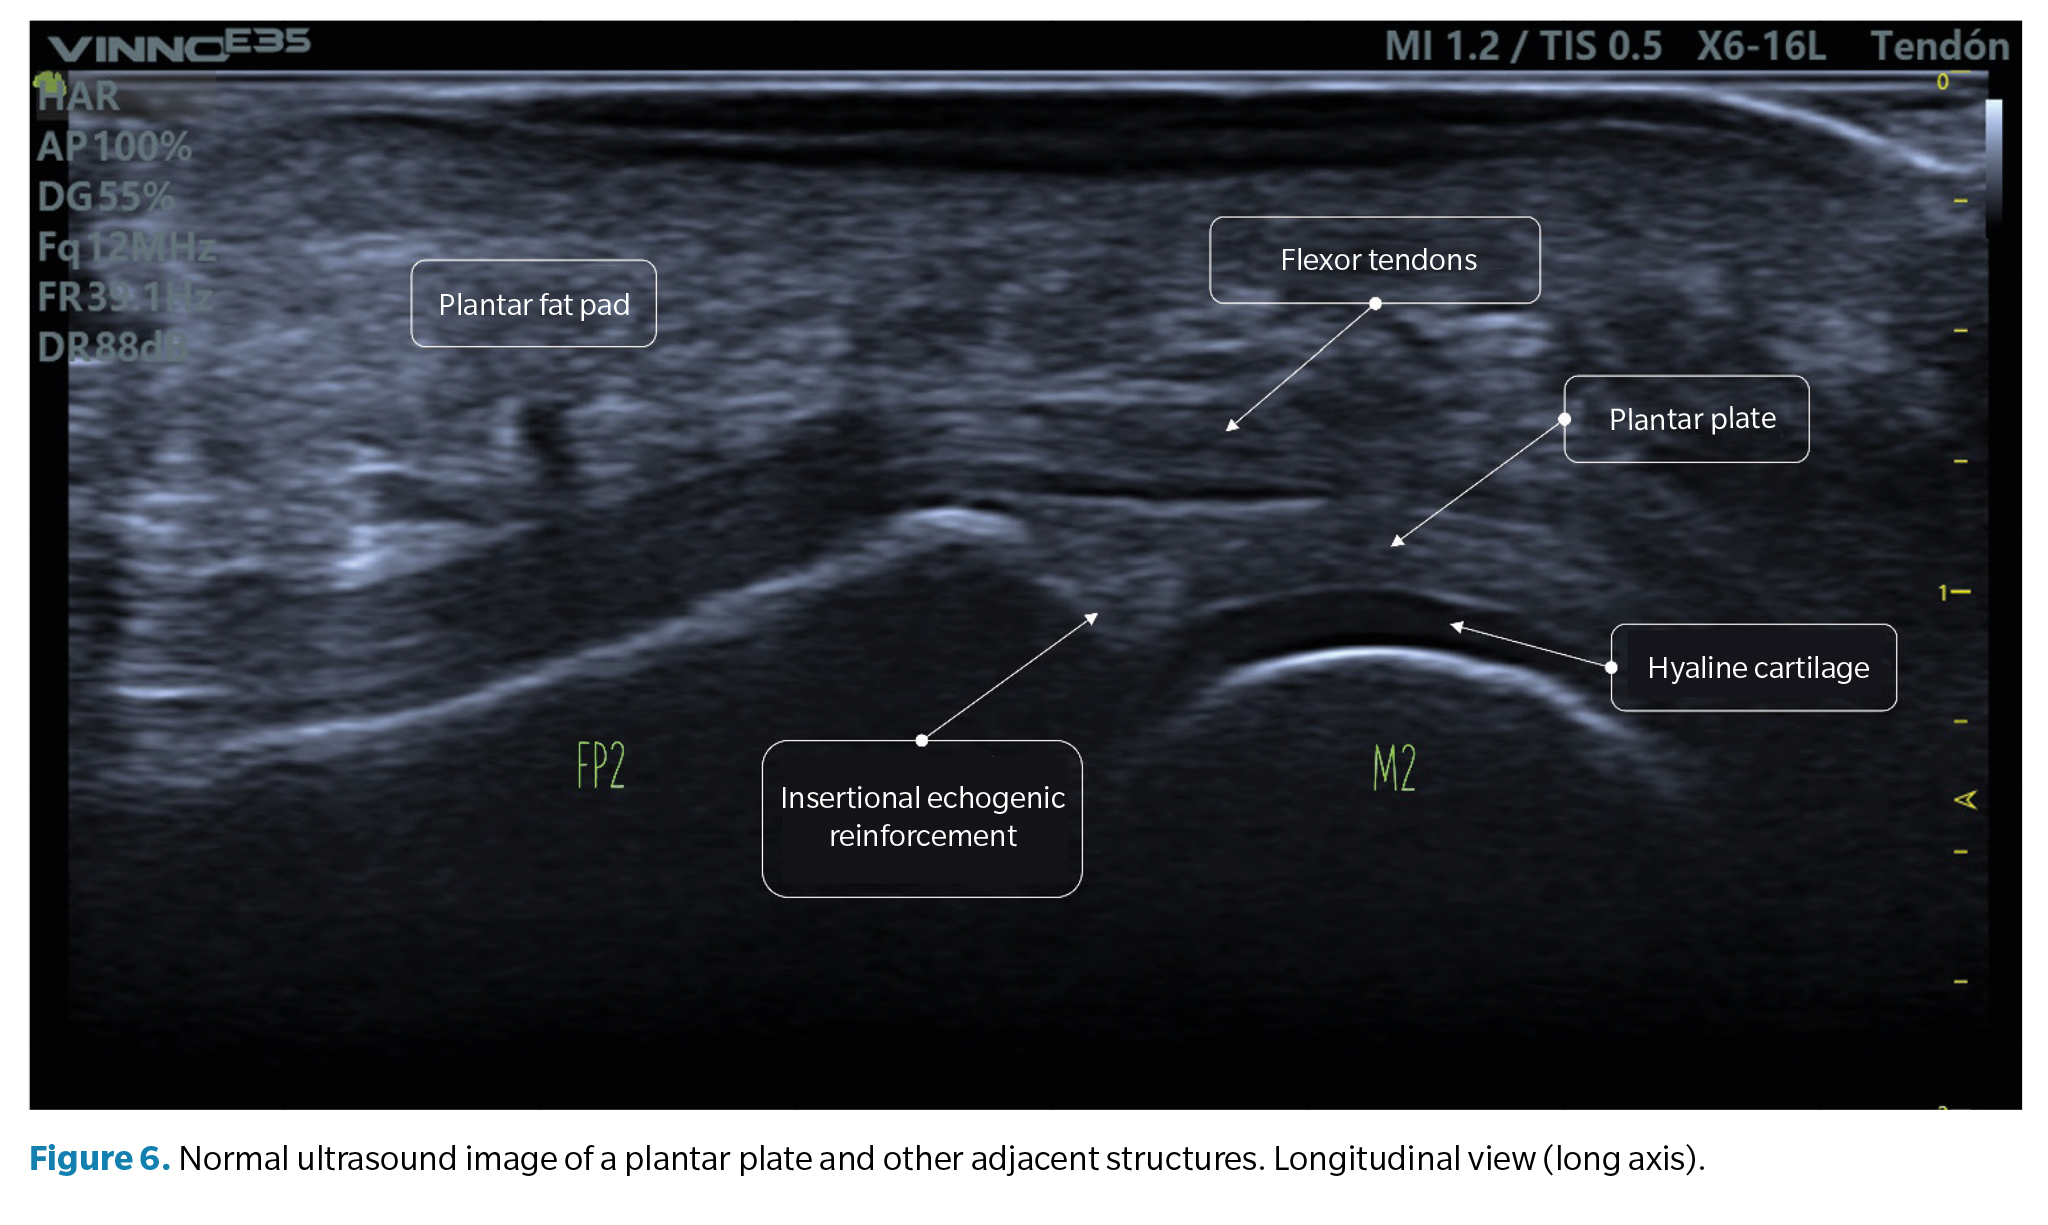

• Longitudinal view (long axis): the normal plantar plate appears on ultrasound as a slightly echogenic curvilinear structure with a homogeneous granular echotexture. This texture allows differentiation, not always well-defined, from the underlying flexor tendons with a fibrillar texture. The articular surface of the plate is precisely defined, bordering the hypoechoic hyaline cartilage of the metatarsal head (Figure 6).

At the junction with the proximal phalanx, which is well-defined, the bone contour is usually smooth, and a more echogenic triangular area may appear in the plate, described as a normal ultrasound finding and possibly representing a higher proportion of collagen fibers. The proximal junction with the metatarsal neck, however, has poor definition on the ultrasound image (Figure 6).

• Transverse view (short axis): the plantar plate will have a curved shape that cradles the metatarsal head. The echotexture is equally granular, although in this exam, the mottled appearance may be more heterogeneous, reflecting the longitudinal arrangement of collagen bundles. The flexor tendons can be seen over the plate and can be easily identified using anisotropy maneuvers (Figure 7).